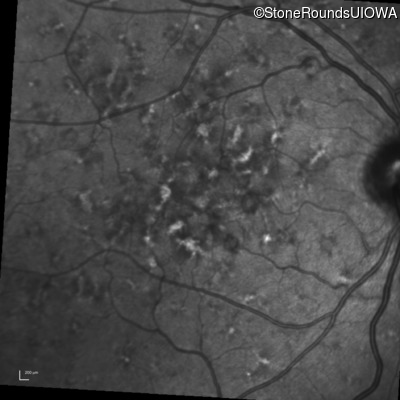

Blue Autofluorescence - Right - 20/20 -1

Exemplar